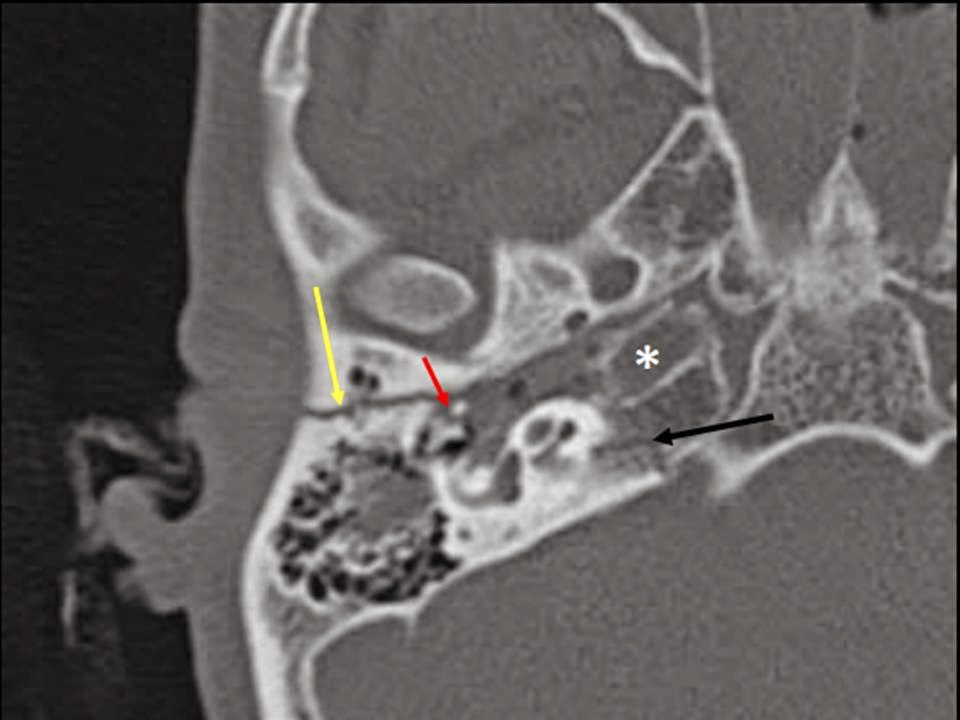

Fracturas del peñasco:

Los traumatismos del oído medio y externo son frecuentes y están asociados a fracturas del hueso temporal. Las fracturas se pueden clasificar en:

- Fracturas Longitudinales: Son las mas frecuentes. Producto de golpes en la región temporal o parietal siguiendo el eje del peñasco

- Signos y sintomas de esta fractura: Desgarro de la piel del CAE y membrana timpánica causando otorragia, alteraciones en la articulación incudoestapedial, existe un compromiso del nervio facial en un 20%

- Fracturas Transversales: Ocurre alrededor del 15% de los casos. El compromiso de los agujeros de la base del cráneo es frecuente al igual que el compromiso de la cápsula ótica, Compromiso del nervio facial es frecuente.

- Signos y sintomas de esta fractura: No presenta otorragia, vértigo severo, hipoacusia neurosensorial, hemotímpano sin desgarro de la membrana timpánica

- Fracturas Mixtas: Suelen asociarse con traumatismos severos y múltiples, pueden afectar al oído medio y oído interno

- Signos y sintomas de estas fracturas: Vértigo, hipoacusia neurosensorial o conductiva, hemotímpano, desgarro de la piel del CAE y parálisis facial